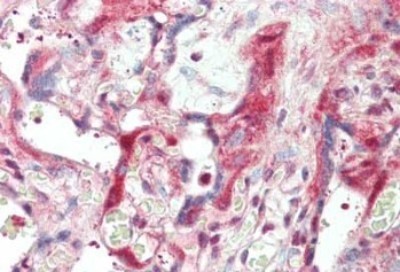

- Main image

- Experimental details

- Immunohistochemistry: Laminin beta 1 Antibody [NB120-6571] - Tissue: skin. Fixation: formalin fixed paraffin embedded. Primary antibody: Anti-Laminin at 5 ug/mL for 1 h at RT. Secondary antibody: Peroxidase rabbit secondary antibody at 1:10,000 for 45 min at RT. Staining: Laminin as precipitated red signal with hematoxylin purple nuclear counterstain.